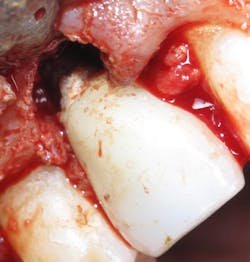

The dental endoscope is invaluable for preventing and treating peri-implantitis. The endoscope allows for visualization of residual cement, microgaps, and open and overhanging crown margins (figure 3). Inspection with the endoscope at the time of restoration can be a kind of insurance policy for the doctor to be sure that any conditions that would cause iatrogenic problems are not present (figure 4).

Figure 4: A dental implant with residual cement during surgical repair. A dental endoscope would have shown this cement at the time of restoration, saving the patient time and money.